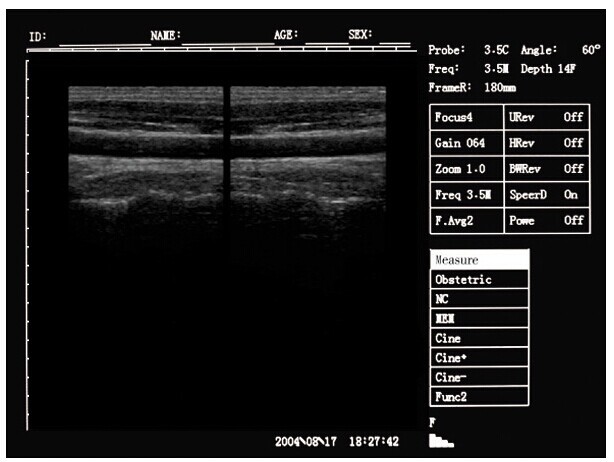

Portable ultrasound machine Laptop Ultrasound machine SU-7S with CE Images |